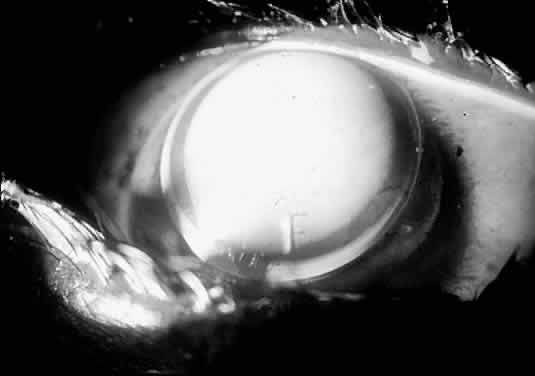

I believe that the best way to rehabilitate the keratoconus patient is to fit Soper-type keratoconus lenses.21,28 This type of lens is a bicurved lens; thus, a steep central posterior curve (CPC) vaults the cone, and a relatively large peripheral curve fits the peripheral cornea outside the cone (Fig. 16). This lens is fitted based on the concept of sagittal depth, and calibrated diagnostic lenses are placed onto the eye until a proper fluorescein pattern is observed.

Fig. 16. Soper keratoconus lens. Note the steep central posterior curve (CPC) and the flatter peripheral curve. Sagittal depth is calculated for the diameter of the CPC, not the diameter of the entire lens.

If a diagnostic lens produces an air bubble or extreme fluorescein pooling, then that lens has too large a sagittal depth (too steep), and a lens with a smaller sagittal depth should be tried. A flat lens produces apical touch, requiring that a steeper lens be tried next. The correct lens barely vaults the cone, demonstrating a uniform central fluorescein pattern, as demonstrated in Figures 17 through 19.

Fig. 17. Soper keratoconus lens, the sagittal depth of which is too great. Copious fluorescein is pooling centrally. If this lens were any steeper, it would trap an air bubble centrally

Fig. 18. Soper lens bearing on the cone. This lens's sagittal depth is too small. Occasional air bubbles may be trapped peripherally when a keratoconus lens is too flat.

Fig. 19. Well-fitting Soper keratoconus lens. Fluorescein pattern is uniform over the cone.